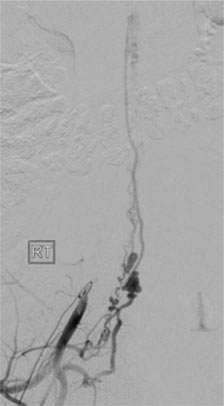

Figure 1: Spinal AVM

Spinal vascular malformation is a very rare condition. It is an abnormal tangle of blood vessels on, in, and/or near the spinal cord (Figure 1).

Depending on where a malformation is located, it is classified as:an intramedullary arteriovenous malformation (AVM within the spinal cord tissue), a pial arteriovenous malformation (AVM on the surface), a dural spinal arteriovenous fistula (DAVF within the membrane that covers the spinal cord), or an epidural arteriovenous fistula (Epidural AVF on the surface of the membrane that covers the spinal cord).

Intramedullary and pial AVMs are considered to be congenital conditions (Figure 1). Larger malformations tend to cause symptoms in a younger age group than smaller AVMs. In fact, smaller malformations can be completely silent. Symptoms from spinal AVMs can occur in a gradual fashion or acutely and dramatically. The symptoms include abnormal sensation in the body, back pain, weakness in the extremities, sexual dysfunction, and bowel/bladder disturbances.